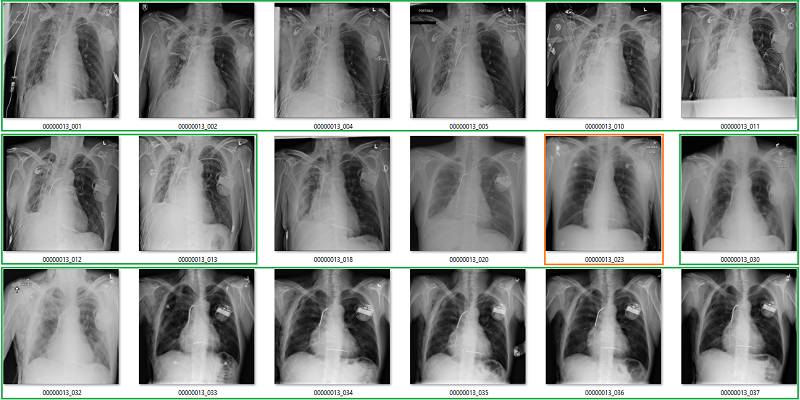

该模型的表现非常像 Summers 等人的研究,我的模型可以明确地从这些标签中学到一些知识,但模型具体学到了些什么?

以下是模型的预测以及它们与数据集中的标注所做的比较:

真正类

绿色是真正类,其它的是错误的标签。

真负类

前 18 张有 1 到 2 个有争议,后面 18 张中红框都是错误的。

假正类

红色的都是错的,数据集中也出现了旋转和扭曲等异常情况(用红色问号标记)。

假负类

红色部分为严重错误标注。

尽管 AUC 是 0.7,但与标签错误率一致,我们的分类性能非常糟糕。该模型无法忽略错误的标签,输出合理的预测,它对标签噪声不具备鲁棒性。最重要的是,AUC 值没有反映诊断性能,这是一个很大的问题。

这一 AI 系统学习可靠地输出无意义的预测。它学习图像特征的方式使「opacity」的案例变得几乎没有模糊性,而「no opacity」的案例被判断为严重不正常的肺。